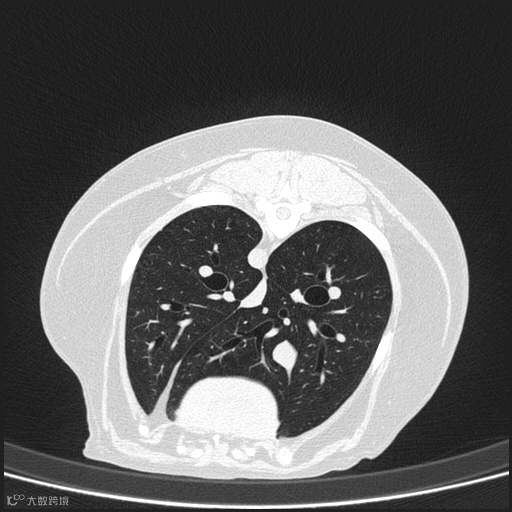

图像中能够显示的最小细节。观察图像中能否清晰识别小的解剖特征,并排除模糊或失真的情况。高分辨率图像可以清晰地显示小的解剖结构和病变。

肺部高分辨